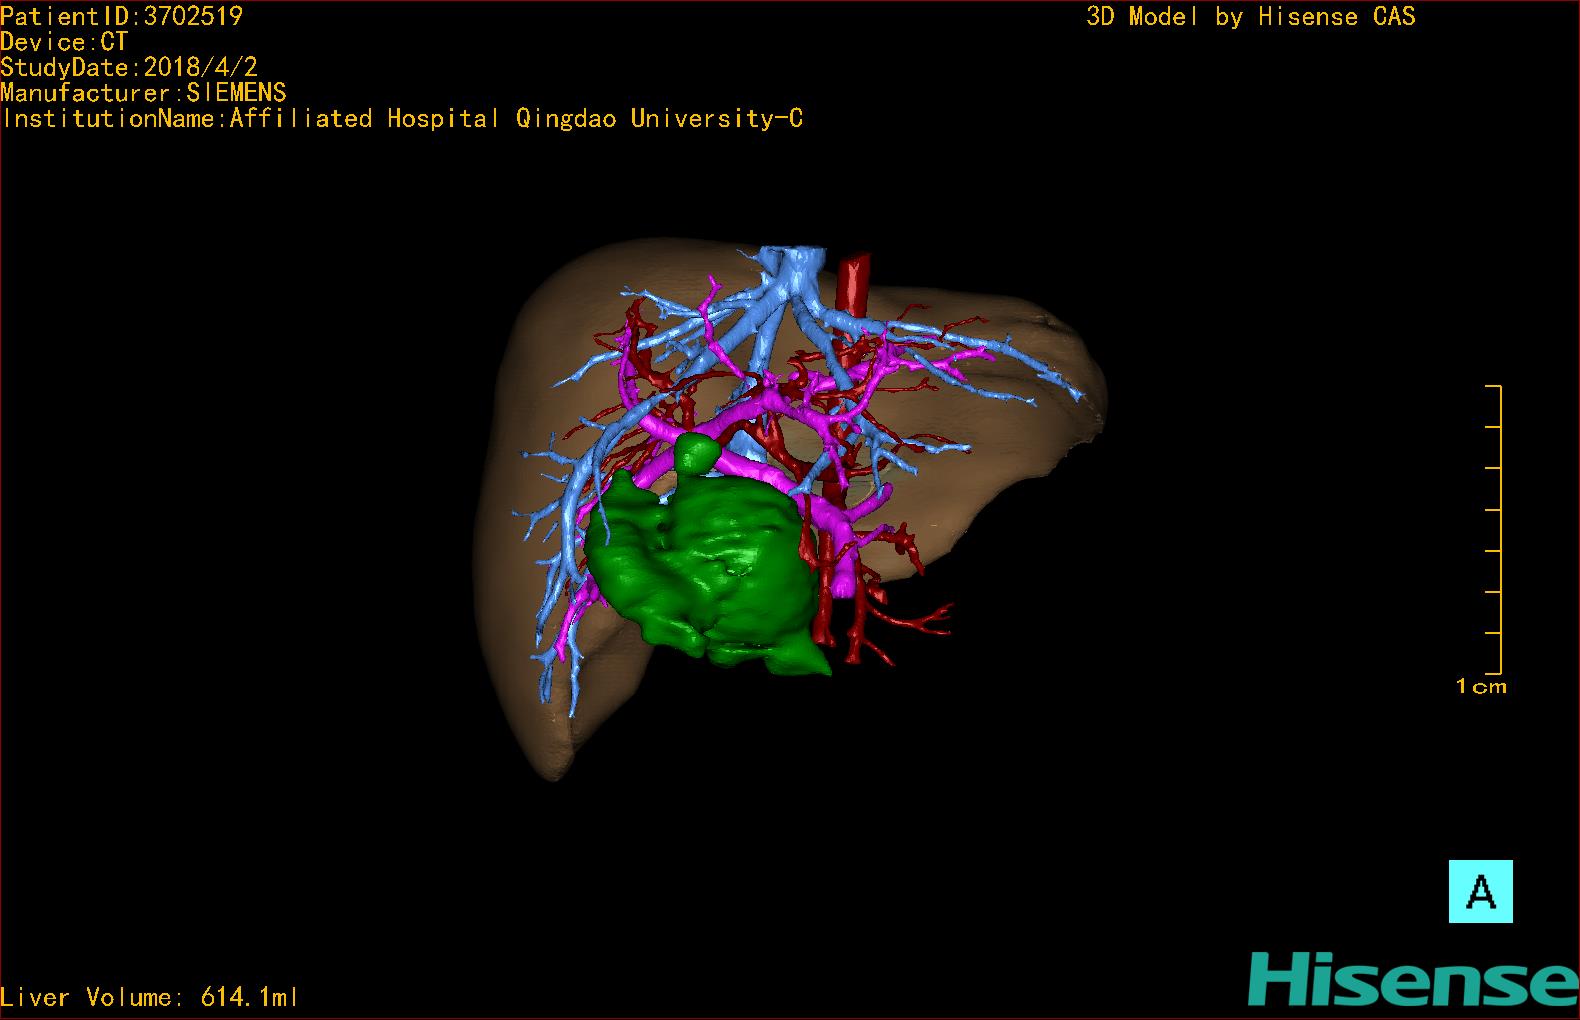

10、三维重建虚拟肝脏、胆道显像技术

三维虚拟肝脏技术是在二维影像学资料如CT等图像的基础上,通过三维重组软件和工具,比如青岛大学附属医院与海信医疗集团联合自主研发的海信计算机辅助手术系统(Hisense Computer Assisted Surgery,Hisense CAS),目前已投入临床并指导实际应用,利用该类系统对二维影像学的数据资料进行三维立体分析,重组形成立体的、有空间结构的、虚拟的肝脏三维图像。这项技术较传统的二维平面成像技术,有着明显的优势,3D虚拟肝脏技术可以构造出一个虚拟的、可视化的肝脏模型。通过对这种模型的观察,可以很容易地分辨出肝脏器官的组织结构、解剖特点,直观研究肝外胆总管的形态差异,明确肝内胆管的形态、走形、是否合并扩张、狭窄及结石,胰胆管合流的形态及共同通道内是否有狭窄、扩张和结石等病变情况,预先规划处理可能合并存在的肝内胆管扩张、狭窄或其他复杂胆道畸形,清晰地显示肝内脉管系统,包括门静脉、肝动脉及肝静脉的走行、分支,并可多角度、全方位观察病变胆道与其周围重要血管尤其是伴行的门静脉之间的解剖关系,大大提高了外科医师在术前对肝脏内部各管道结构及其变异判断的精确性和可靠性,精准地对病变进行判断和评估,还可根据患者自身的病变特点,制定出合理、个体化的手术方案,最大限度地降低术中和术后并发症发生率,并术中导航实时指导手术,提高手术的精准性和成功率。

图10:先天性胆管扩张症囊肿型三维重建虚拟肝脏、胆道显像

a 图为术前二维CT扫描图像,箭头所示为肝内胆管扩张;b 图为CT经多平面重组技术(MPR)图像后处理所得的重建图像,可显示胆总管明显扩张合并肝内胆管扩张;c 图为MRCP显示胆总管呈囊柱状扩张,直径>1 0 cm,伴肝内胆管扩张;d 图示Hisense CAS三维重建清晰显示肝脏、胆道系统及其与门静脉、肝动脉、肝静脉等之间的空间解剖关系;e 图示Hisense CAS可从任意角度以不同脏器组合显示,明确胆道系统与其伴行的门静脉系统的空间解剖关系;f 图示胆道系统立体形态及与肝脏整体的空间关系,箭头处显示肝内胆管狭窄部位发生于左右肝管汇入肝总管处。术前规划需行肝内胆管扩大成形术。